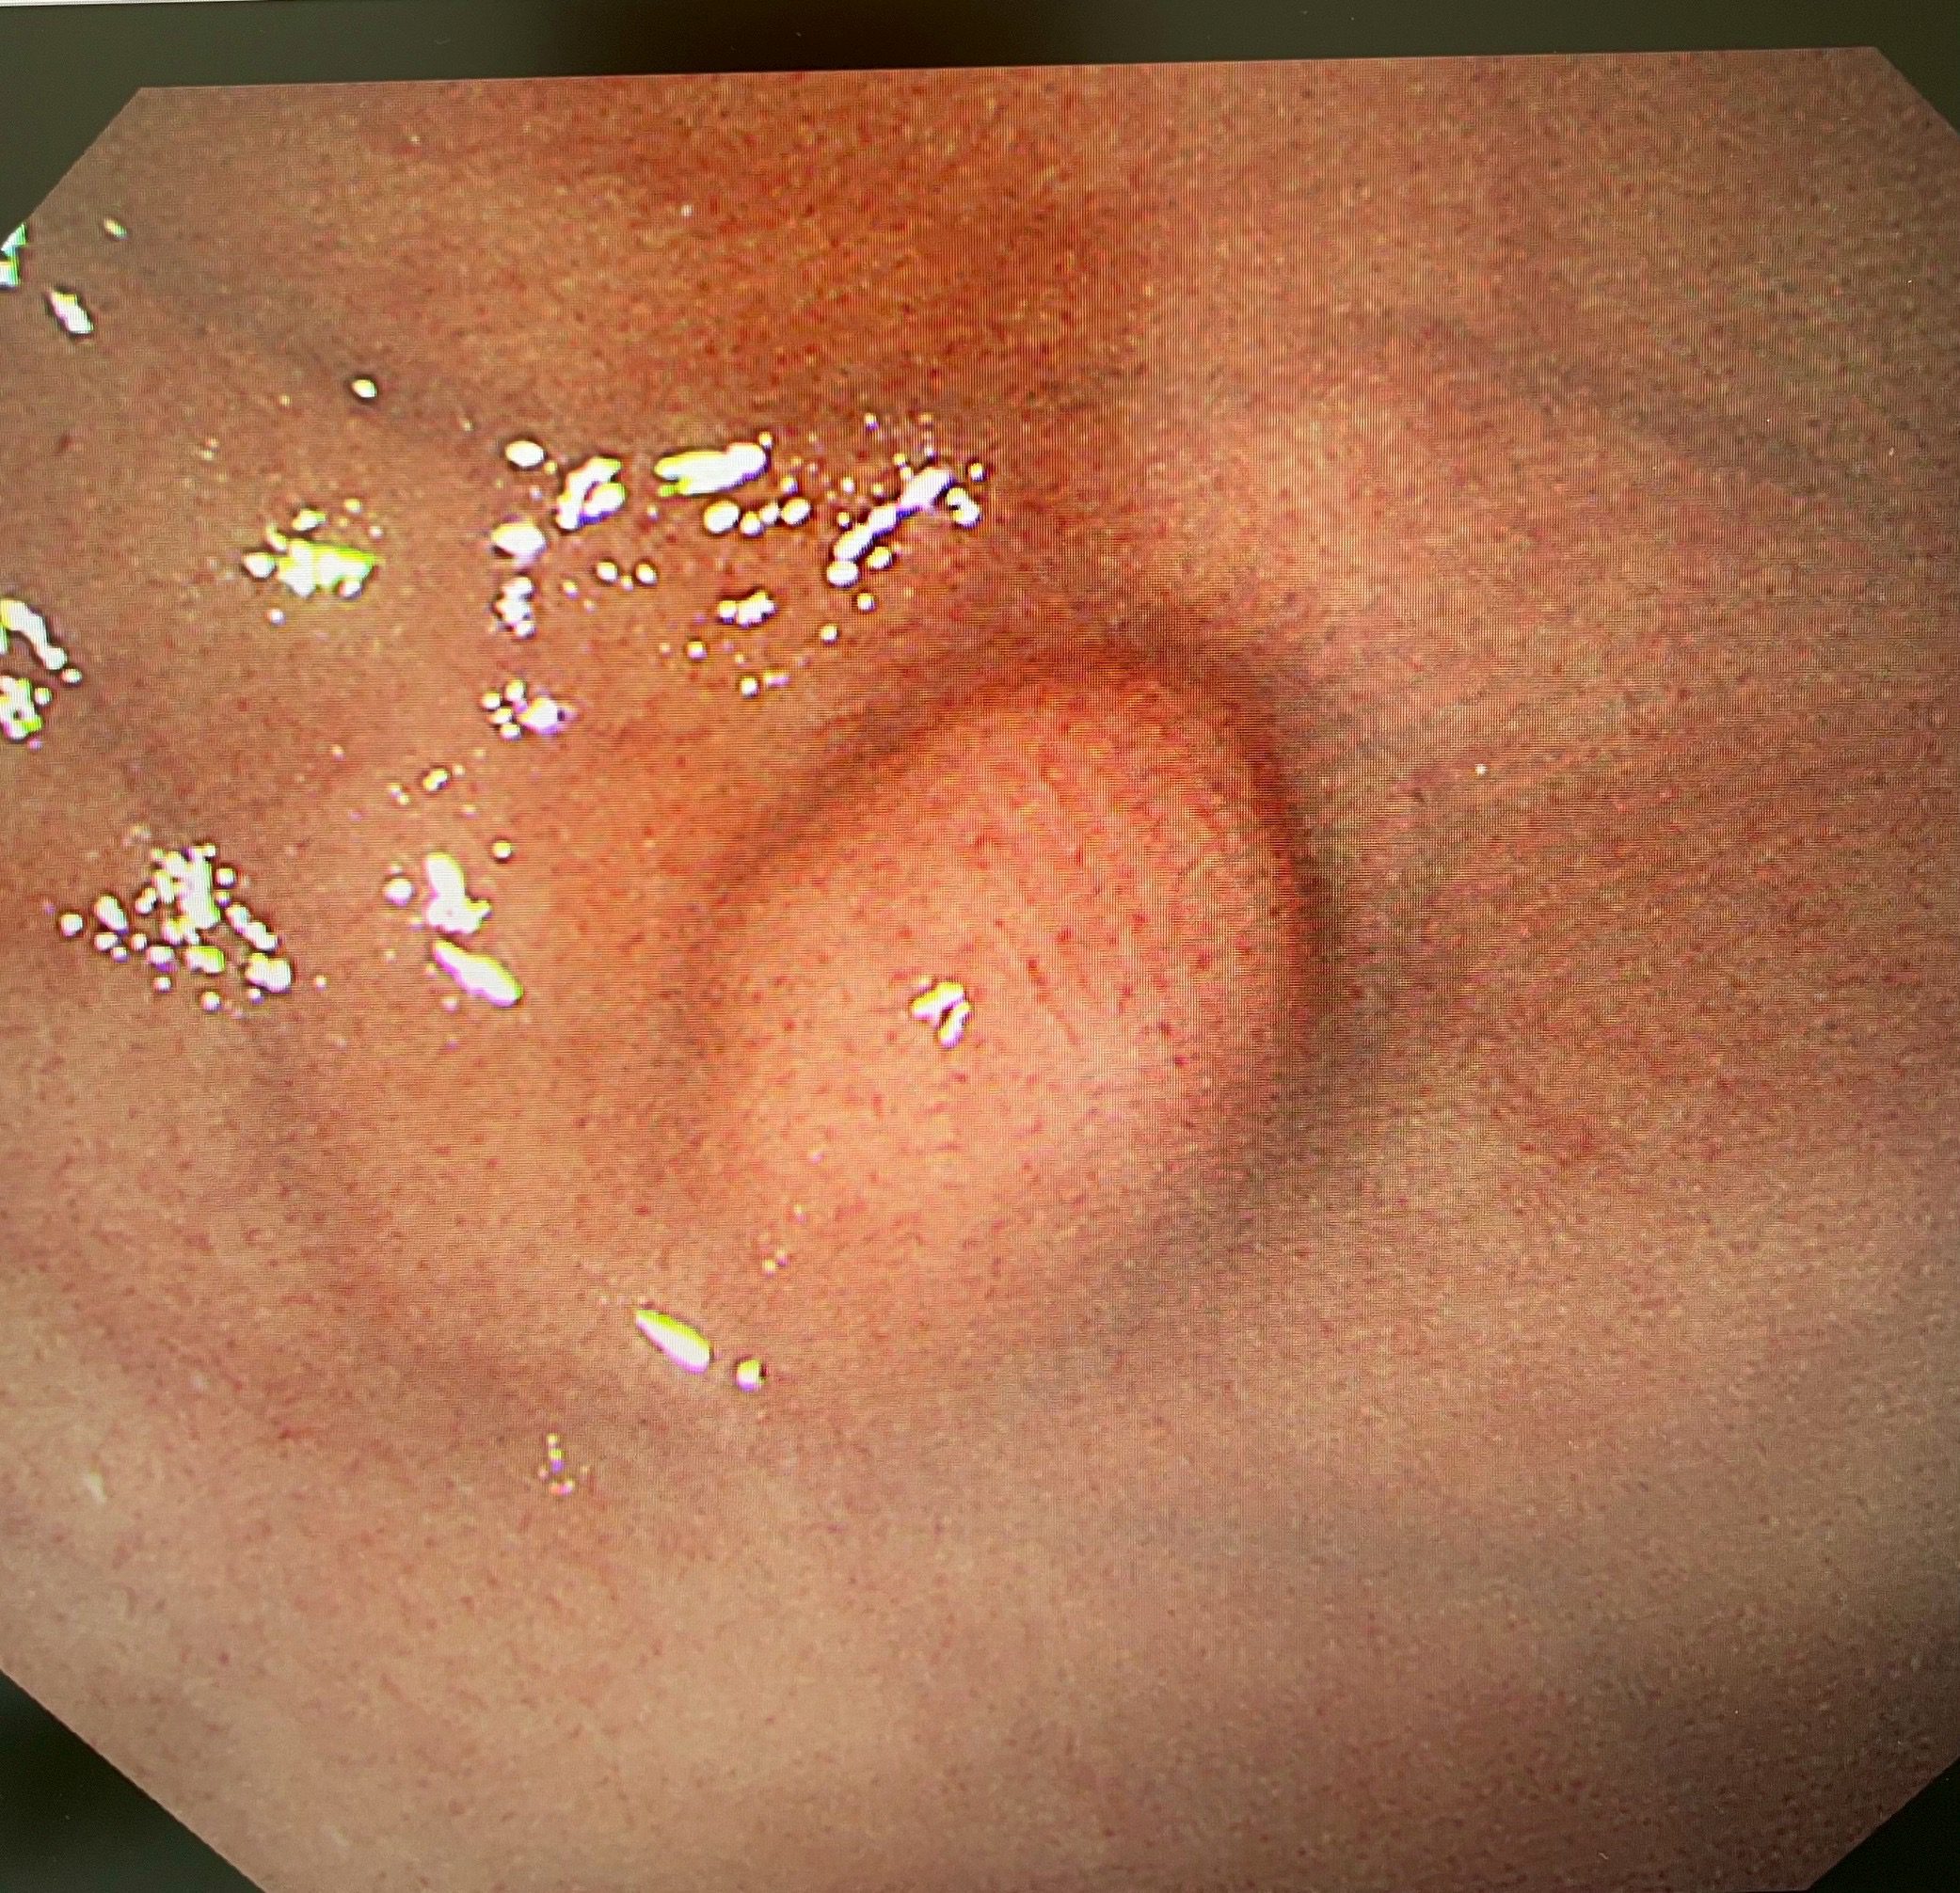

該患者轉至陳鴻運醫師門診後,醫療團隊為她安排了上消化道內視鏡、內視鏡超音波(EUS)及電腦斷層檢查。內視鏡超音波檢查顯示,腫瘤已生長至胃壁第四層(固有肌層),但幸運的是沒有附近淋巴結及遠處轉移的跡象。

「內視鏡超音波是評估黏膜下腫瘤的黃金標準工具」,陳鴻運醫師說明:「它能清晰顯示胃壁的五層結構,準確判斷腫瘤的起源層次、大小和特性,幫助我們制定最合適的手術方案。」